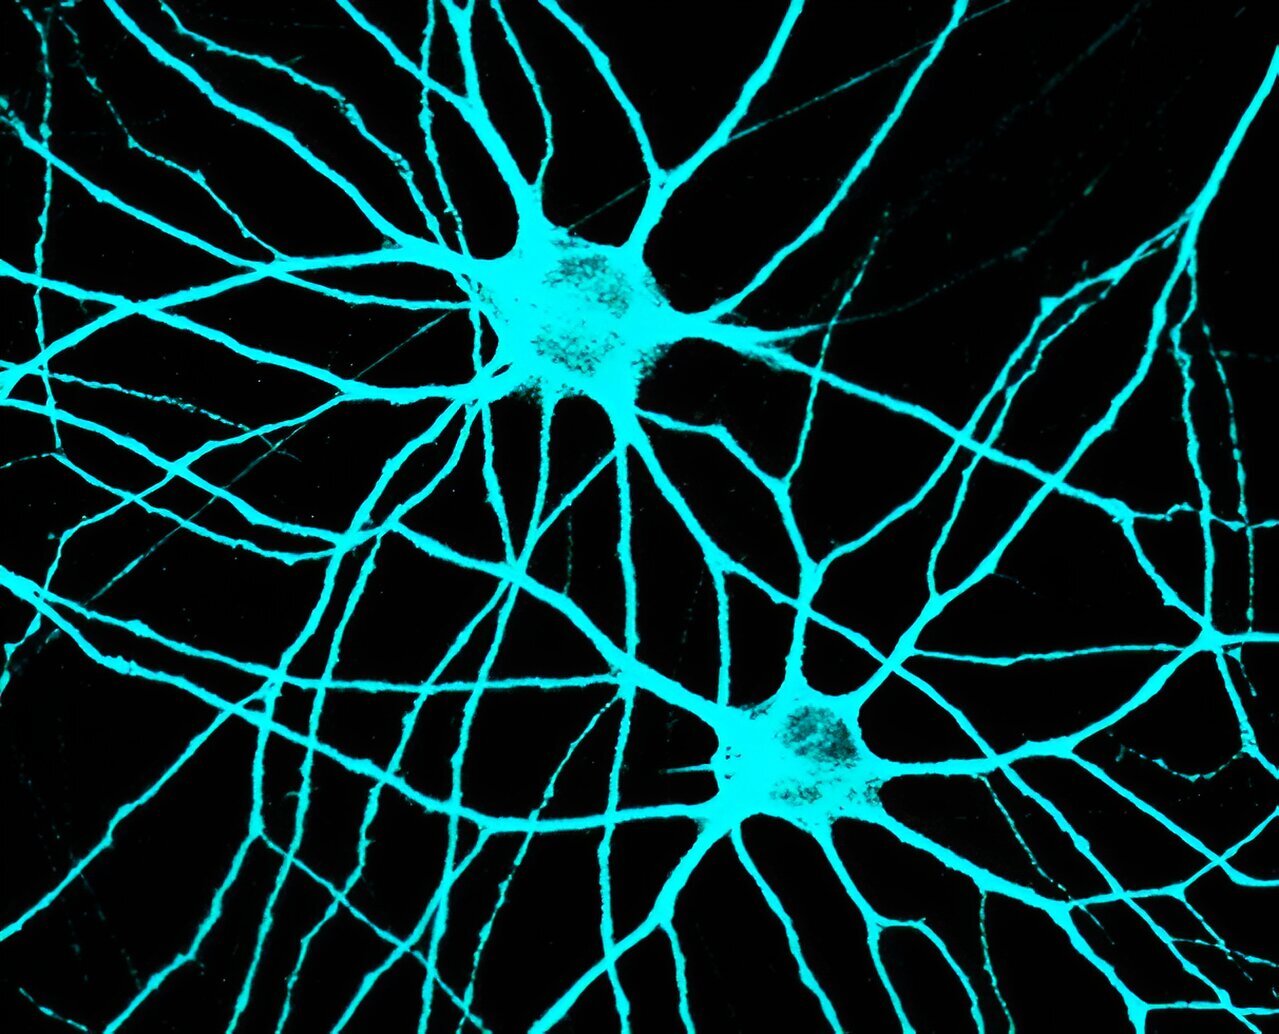

Статья, опубликованная в журнале Proceedings of the National Academy of Sciences, посвящена тому, как нейроны в мозге передают информацию друг другу через специальные межклеточные структуры, называемые синапсами. Эти образования играют ключевую роль в регуляции многих процессов нервной системы с помощью электрохимических сигналов. Нарушения в генах, отвечающих за развитие синапсов, могут вызывать серьезные психические расстройства.

Для изучения этих взаимосвязей команда Чанды использовала модель мозга, созданную из человеческих нейронов, полученных из стволовых клеток. С помощью инструмента редактирования генов CRISPR-Cas9 ученые смогли генетически манипулировать системой и подтвердить роль Gephyrin в формировании синапсов.

Для этого команда использовала человеческие стволовые клетки для создания мозговых клеток, имитирующих свойства человеческих нейронов и синапсов. Затем ученые провели высокоточное сканирование этих нейронов и отследили их электрическую активность, чтобы понять механизмы синаптической передачи.